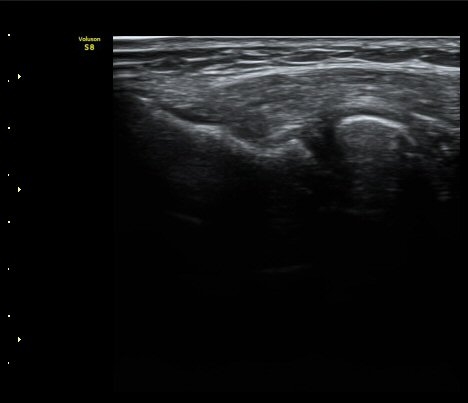

[ÆÈ²ÞÄ¡] Å״Ͻº¿¤º¸¿ì(¿Ü»ó°ú¿°)¿¡ µ¿¹ÝµÈ ¿ä°ñ½Å°æ Èİñ°£ºÐÁö º´Áõ 2

ÃÊÀ½ÆÄ °Ë»ç